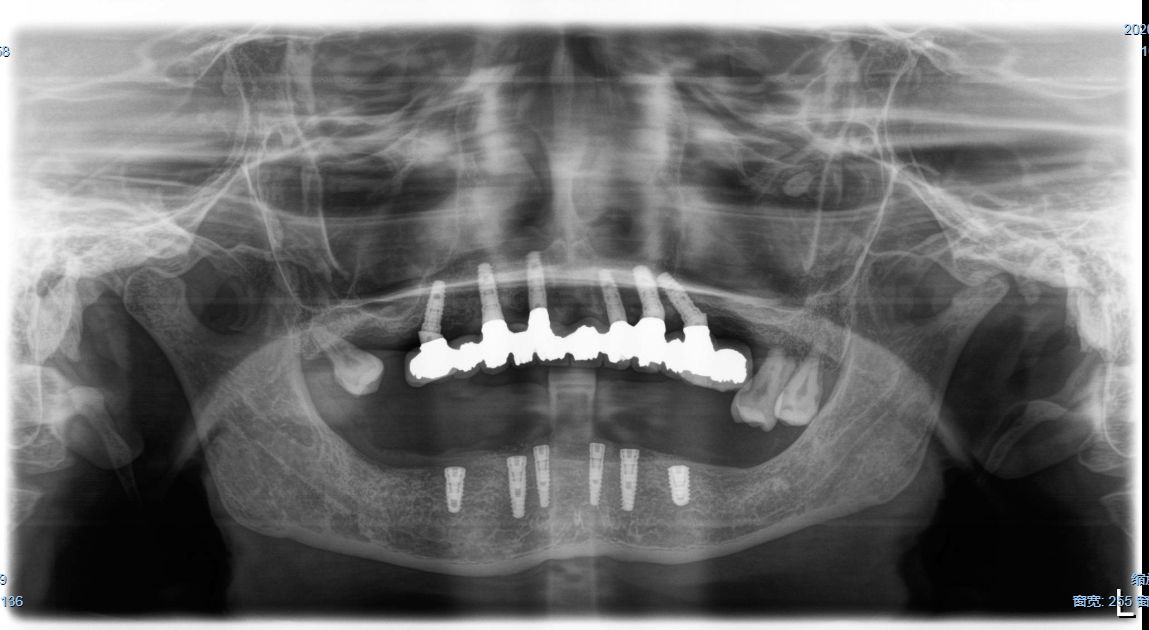

这是一位今天种植牙复诊患者的牙齿的,早期因为牙齿缺失和牙齿松动,严重影响美观,更影响了她的饮食,15年前我为她种了上半口,一直用得很好!但下合的牙因重度牙周病引起牙齿松动和脱落,今年我又为她种了下半口;经过采用种植牙的方式,使得她的牙齿重换新生,患者说:“戴上牙以后什么都能吃,体重还重了许多,很庆幸当时选择种牙这个选择”。

术后图片